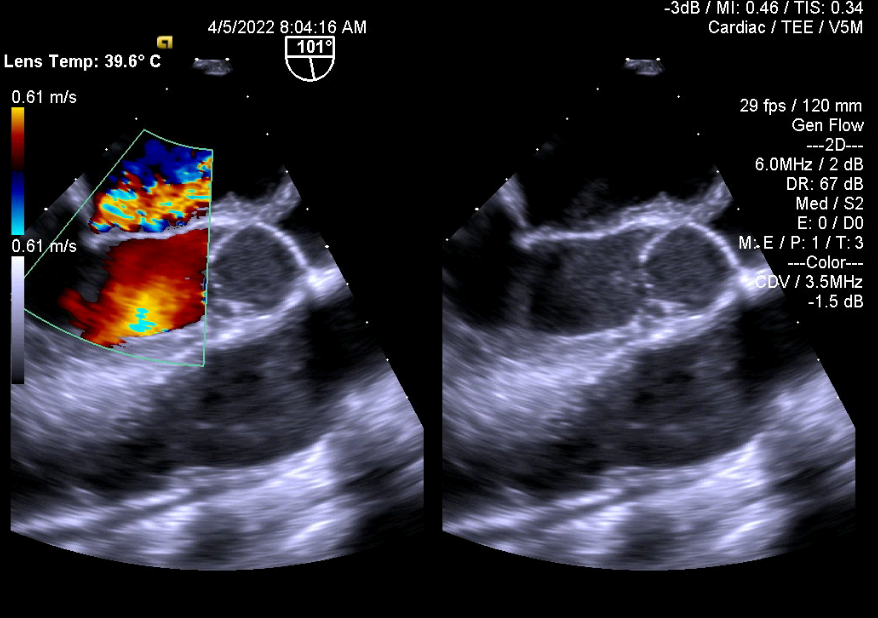

3.Huyết khối tiểu nhĩ trái trên bệnh nhân hẹp van 2 lá (không thấy được trên siêu âm tim qua thành ngực)